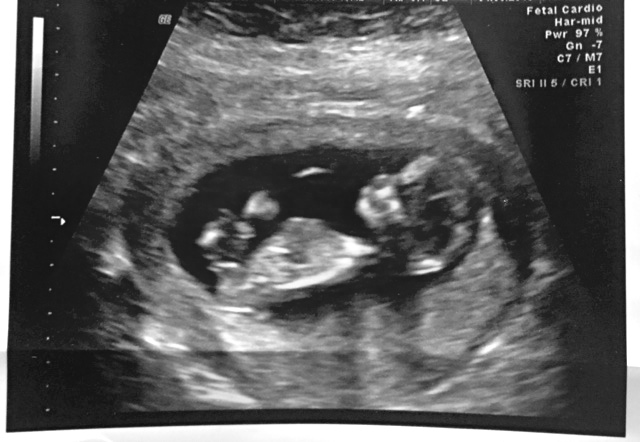

Well I’ve reached my due date (October 21) and still no baby boy. The anticipation makes this wait feel like torture but hopefully baby boy decides to make his appearance soon, as we are all anxiously waiting to meet him.

I am currently at 40 weeks and so ready to pop. I started dilating at 38 weeks but haven’t had any contractions so the waiting game continues. After my 41 week appointment we will schedule induction, hopefully the next day! Hopefully labor starts before that on its own but there is comfort in knowing that soon we will get to meet baby boy. We are very excited to bring him home and prepared to shower him with lots of love.